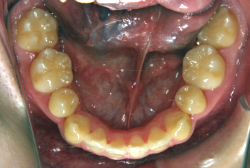

「隙間を閉じたい」という主訴で来院したケースです。診断の結果、「空隙歯列弓+軽度叢生」と判明しましたが、この方の場合は上は隙がある、つまりスペースが余っているのに対して、下は軽度の凸凹がある、つまりスペースが足りないと言う状態でした。

通常、凸凹の症状の場合は、小臼歯を抜歯させていただくのですが、この方の場合は凸凹も軽度で親知らずもないため、非抜歯で対応することになりました。マルチブラケット装置にて治療を開始し、治療期間は11ヶ月でした。治療後は正中の空隙が閉鎖されただけでなく、下の凸凹と下の歯並びの形態そのものが大幅に改善されました。もちろん噛み合わせ的にも正しい状態が確立しています。